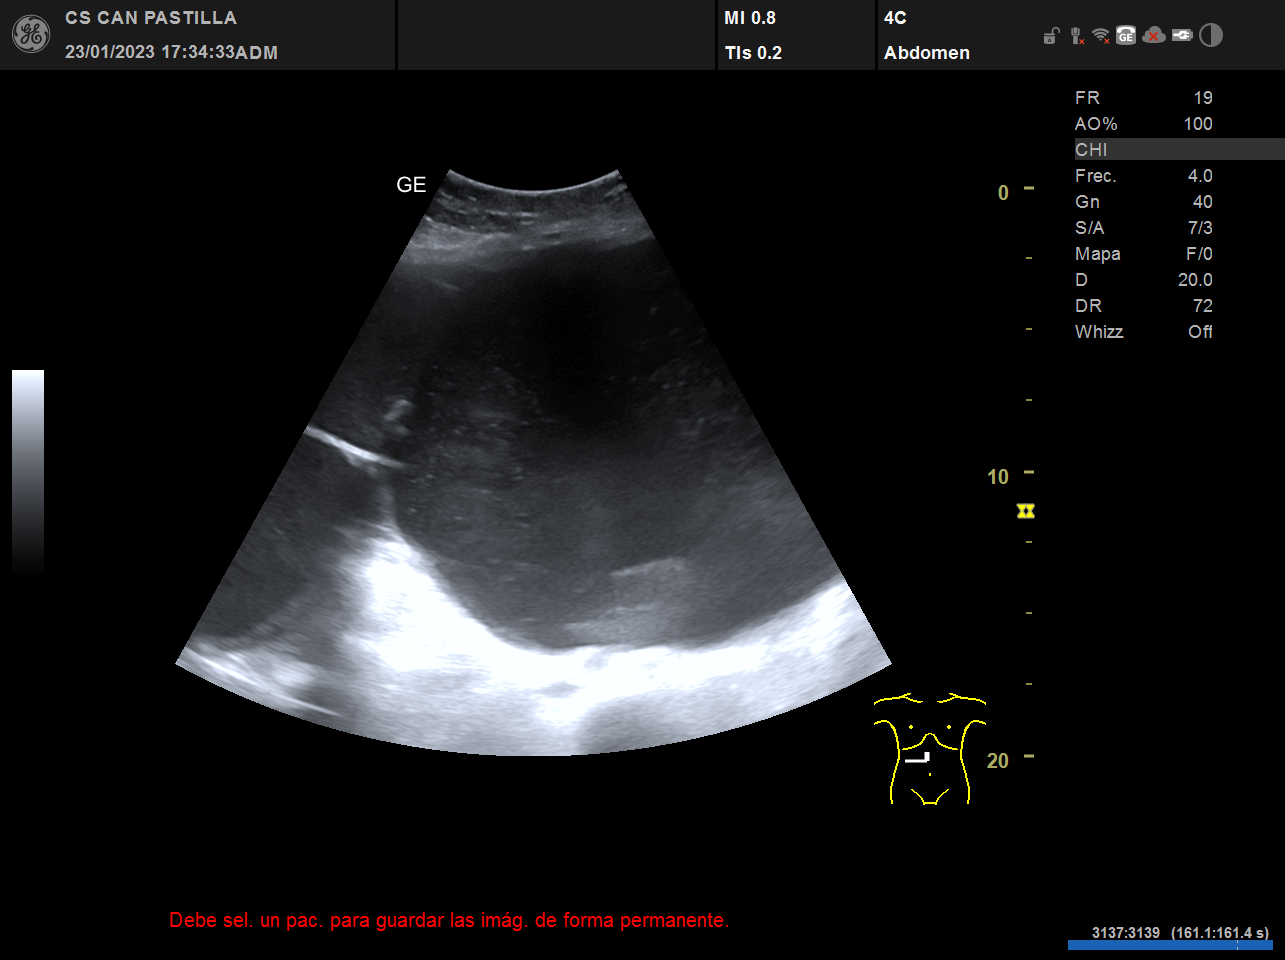

ECO abdominal: destacan imágenes anecóicas con refuerzo acústico posterior y septos en su interior, sugestivas de quistes complejos de gran tamaño (el mayor de ellos de 15 cm de diametro) o un solo quiste tabicado de gran tamaño. Dificultad para observar el parénquima hepático de forma completa, dados la ocupación de las imágenes quísticas.